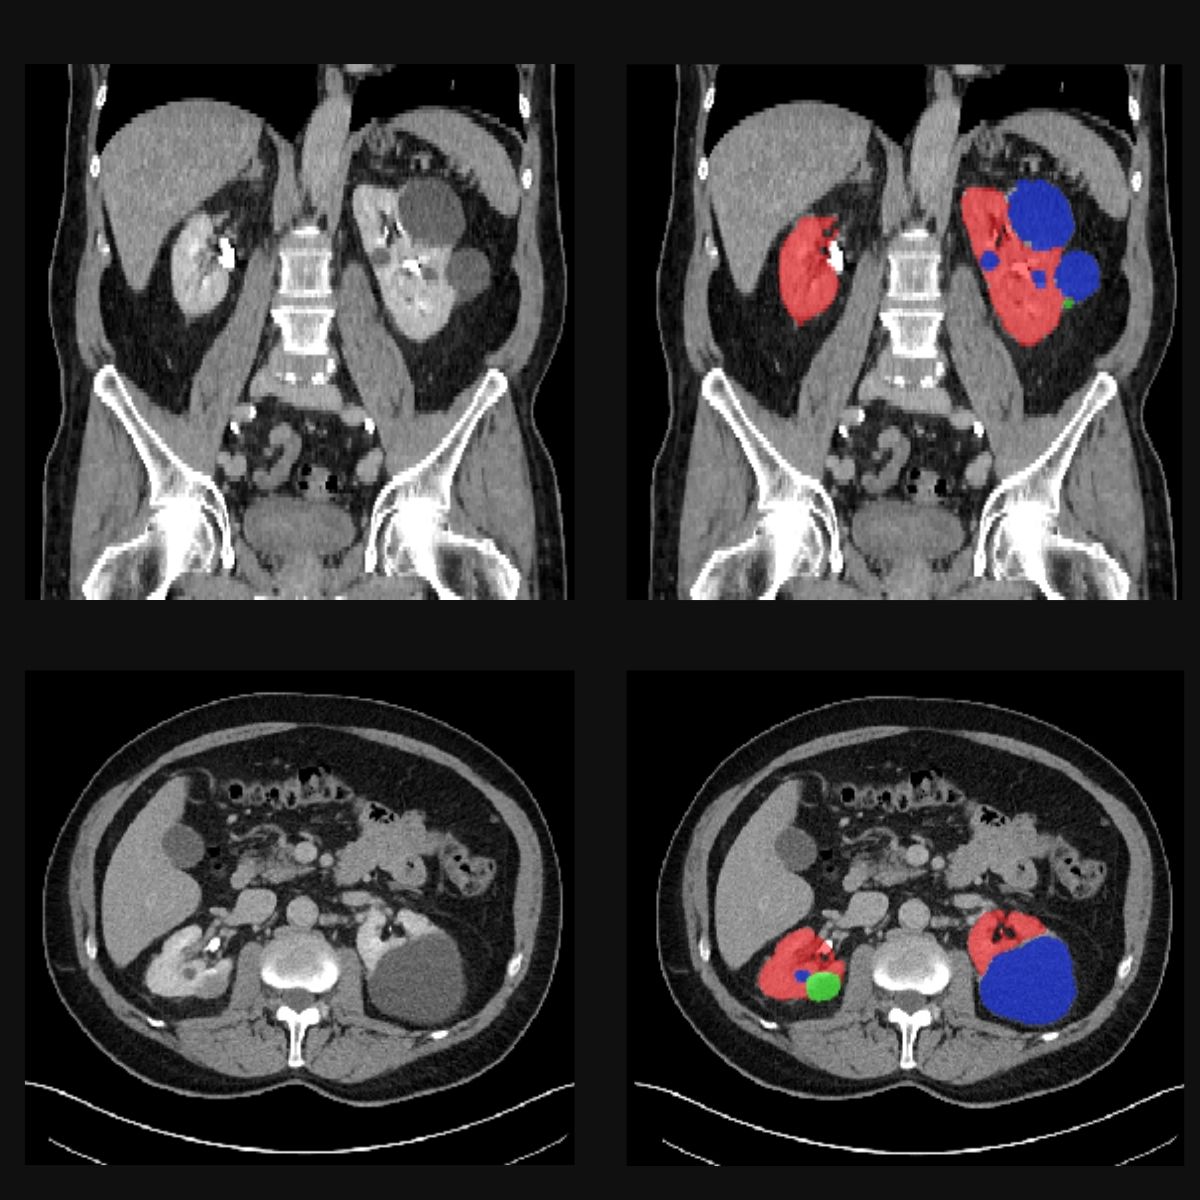

Our goal in COMFORT is to teach AI models to recognise tumours and other abnormalities to make diagnosis faster and more accurate. To this end, our experts manually annotate medical images from CT or MRI scans. This means they mannually outline the organs, in our case the kidneys and the prostates, and abnormalities such as cysts or tumours. By showing the AI model hundreds of annotated images, it eventually learns to generalise its knowledge to new images and recognise organs and tumours by itself.

In the images below you can see such scans: the red areas are the kidneys, green ones are turmours and blue ones are cysts.